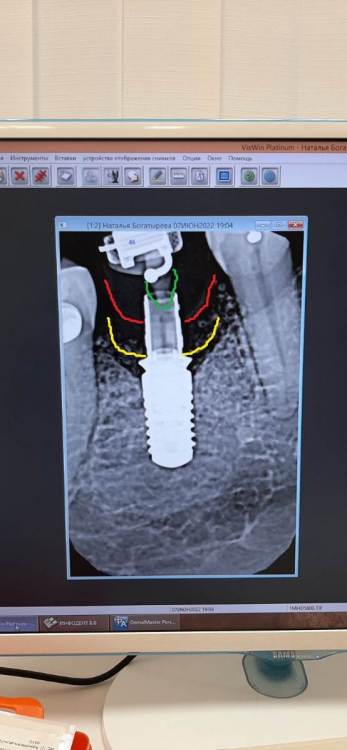

Здравствуйте, возможен ли выход костного материала наружу  через 1 год и 3 месяца после имплантации? Если возможен, то в чем причина? И второй вопрос  - где должна быть коронка, где красные линии, или где желтые, и что это на снимке - отмечено зеленым?

И второй вопрос  - где должна быть коронка, где красные линии, или где желтые, и что это на снимке - отмечено зеленым?

Оба варианта возможны, все зависит от толщины тканей.

Зеленым Вы отметили на снимке заглушку (обычно - тефлоновую) шахты абатмента, она нужна чтобы внутрь ничего не попадало.